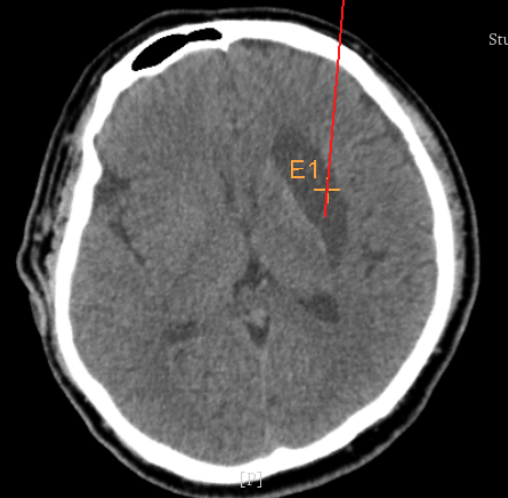

術前CT:血腫已經液化,但仍有占位效應